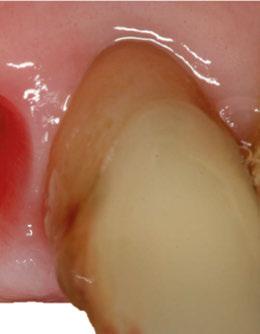

2. Exploración de tejidos blandos

El paciente presentaba biotipo periodontal grueso, con márgenes asimétricos, con recesiones gingivales a nivel de 11 y 13 y pérdida de tejidos blandos interproximales.

En el CBCT observamos pérdida ósea posterior superior debida a la neumatización de los senos maxilares izquierdo y derecho. También podemos observar disponibilidad ósea apical suficiente en dientes antero-superiores para la realización de una Implantología inmediata y corticales vestibulares y palatinas conservadas.